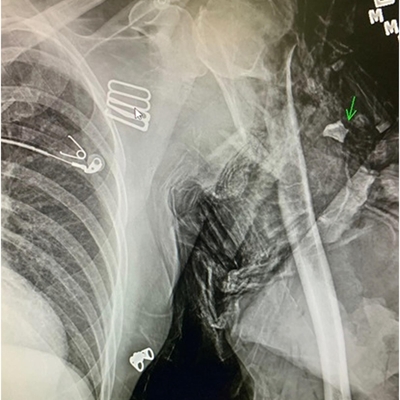

Click on an image below to view more info.